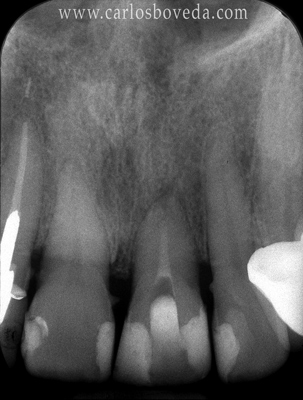

161617